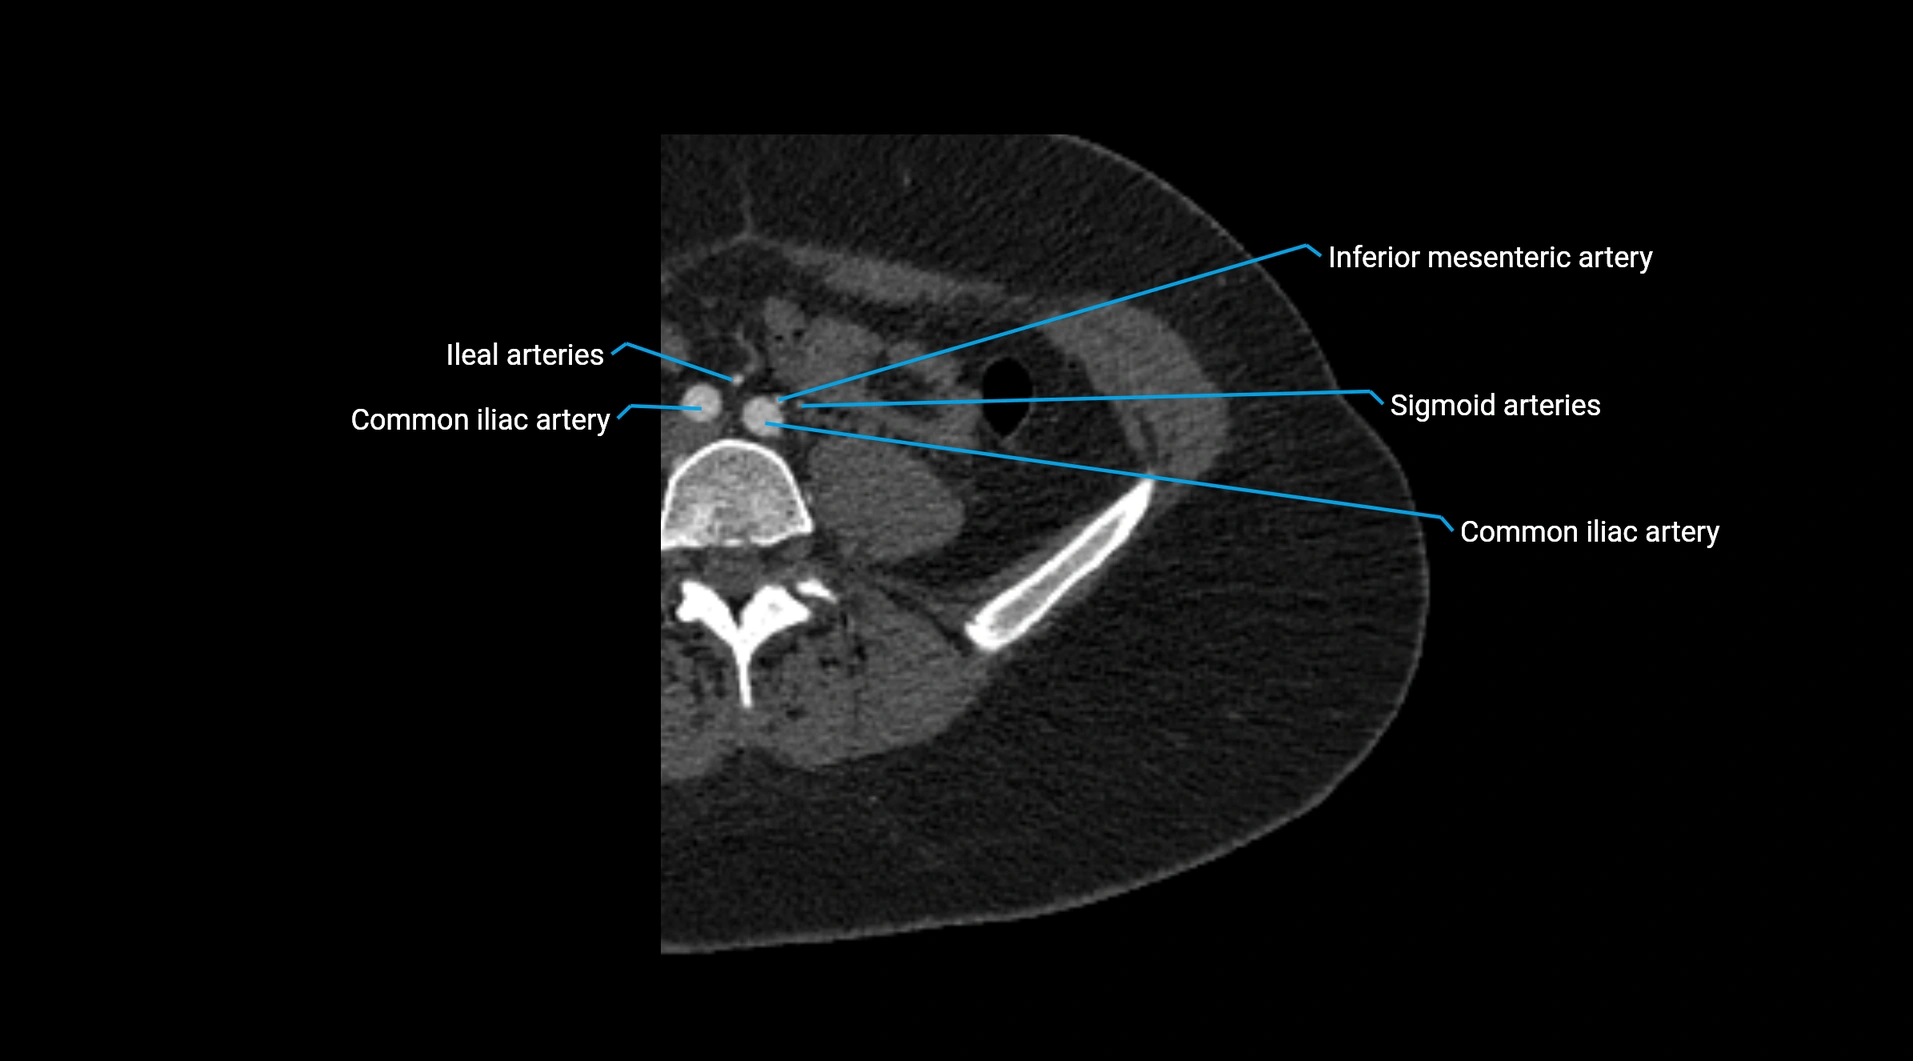

CT images

image

Contrast-enhanced CT (CTA):

• Gold standard for abdominal aortic imaging

• Provides excellent detail of lumen, wall, aneurysm, thrombus, and branch vessels

• Multiplanar and 3D reconstructions help in aneurysm measurement, stent graft planning, and dissection evaluation

• Unpaired visceral branches: celiac trunk, superior mesenteric artery (SMA), inferior mesenteric artery (IMA)

• Terminal branches: right and left common iliac arteries